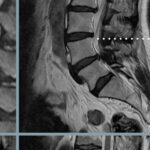

Patologia Lombare